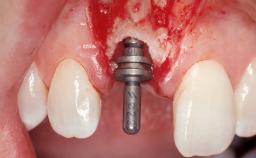

Late Flapless Placement of an Implant in a Maxillary Left Central Incisor Site

A 39-year-old male patient presented with a chief complaint of discomfort and gingival discoloration around his maxillary left central incisor. He was in good general health and was a non-smoker. His past dental history was significant because of the traumatic fracture of tooth 21 in a sporting accident at age 13. Initial dental treatment included endodontic therapy and a full-coverage restoration. The patient became symptomatic 5 years later, when structural failure of the tooth resulted in the dislodgment of the crown. Endodontic retreatment, apical surgery, and post-and-core restoration were performed.

| Bone Augmentation | Horizontal|Staged |

| Bone Volume | Deficient horizontally, requiring prior grafting |